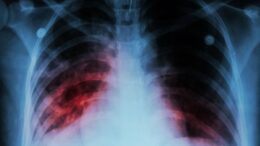

Two healthcare workers get COVID-19 vaccinations on the same day. Both show strong antibody responses initially, but six months later one stays healthy while the other contracts the virus. A…